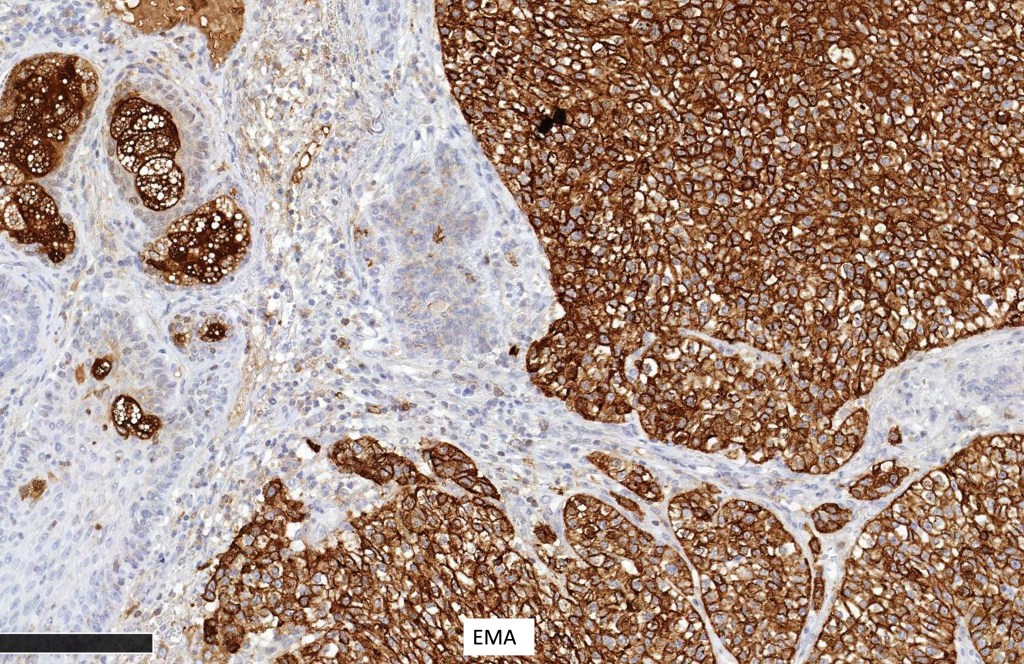

Immunohistochemistry (from the Muir-Torre patient except for EMA which was shared by Dr. Tsheri Dorji